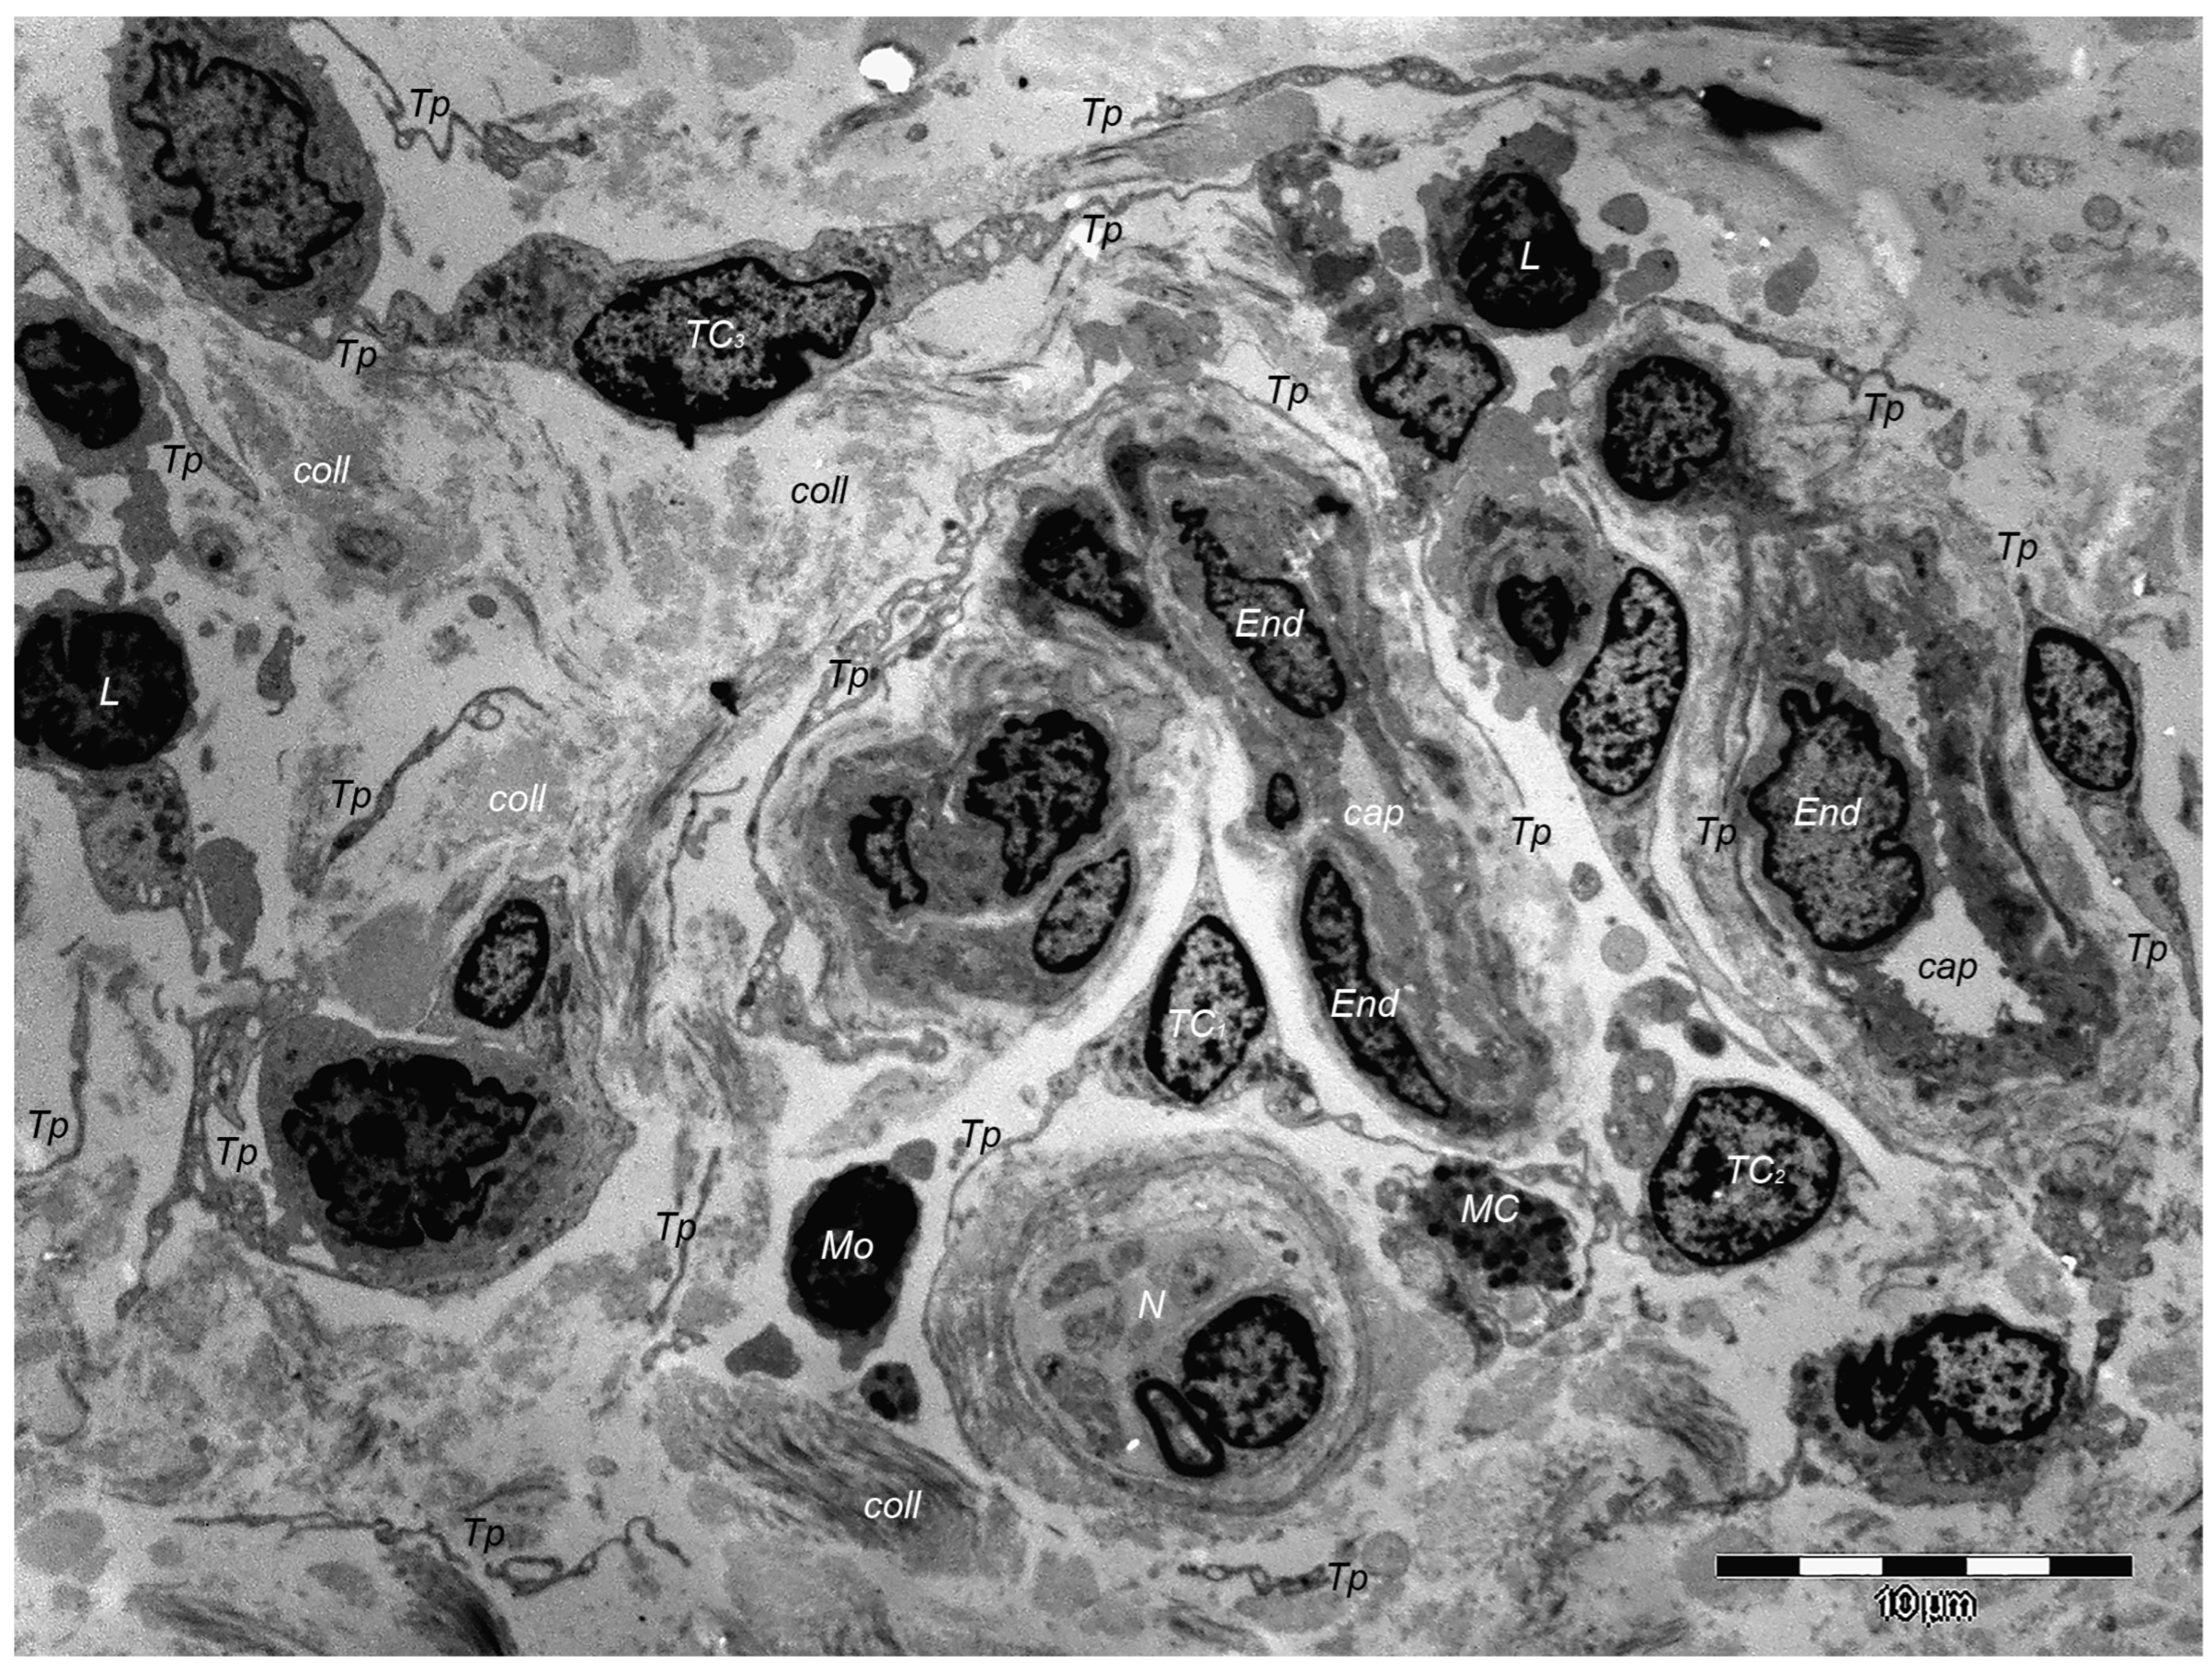

Over one decade ago, a distinct type of interstitial cell was initially documented in the stroma of few different peri-digestive organs [248] and were named telocytes (TCs) due to their morphology and location within tissues. Morphologically, their most prominent trait is the presence of very long cellular prolongations featured by a particular long-lump aspect—termed telopodes (Tps). From the peri-digestive compartment, their presence was afterwards documented in many different other organs from different species, including the (human) skin [249,250,251,252,253,254,255,256,257,258,259,260,261,262,263,264,265,266,267,268,269,270,271,272,273,274,275]. Interestingly, in all these locations, TCs display the same peculiar structural and ultrastructural features, as described in other organs, only with some minor variation in terms of their immunohistochemical phenotype [251,276,277,278,279,280]. Since their presence always features the stroma (connective tissue) of organs, it was understandable to find TCs within skin dermal layers [276,281]. In this location, TCs are grossly distributed in the deeper reticular dermis, in close vicinity to hair follicles strictly boarding the glassy membrane of the hair follicle (Figure 2), sweat glands (Figure 3), or sebaceous glands [282]. TCs are less dense in the superficial papillary dermis. Powerful and complex scanning electron microscopy techniques gave valuable conformational details about TCs and the spatial conformation of their Tps (as they are mostly veil-like structures rather than thread-like cellular prolongations [282]. Also, these techniques proved the complex three-dimensional disposal of dermal Tps (Figure 4), and their disposal in a network involving other TCs (by their Tps) and/or other types of interstitial cells, nerve cells, endothelial cells, or even immune cells [283,284].

However, in terms of ultrastructural phenotype, dermal TCs show a particular double-positive expression for CD34 and PDFGRα. Moreover, in comparison with the connective tissue, mostly present in interstitial cells—the fibroblasts (Fbs)—TCs possess a characteristic positive expression for epithelial-derived neutrophil-activating peptide-78 (ENA-78) and granulocyte chemotactic protein 2 (GCP-2) [10], molecules also found within the platelets’ α-granules. Contrarily, dermal Fbs have a characteristic positive expression for CD90 (procollagen type I), and supplementarily, ELISA testing has confirmed their differential expression for 37 other cytokines, which are more highly expressed than in TCs (IL 5, MCP-3, MCP-4, MIP-3, angiogenin, and thrombopoietin) than Fbs [11].

Of course, corroborating structural data and immunohistochemical data many presumptive roles were suggested for dermal and non-dermal TCs, including intercellular signaling [285], interstitial homeostasis [11], vascular homeostasis [284], (neo)angiogenesis [12], wound healing [286]. Roles of nursing cells either in epithelial stem cells or implications in skin immune physiopathology (interactions with mast cells) are suggested, considering the cytokine/immune profile of TCs. Moreover, these hypotheses consider TC networking within normal tissue and, moreover, TC-specific localization within reticular dermis, in close vicinity to skin adnexa, blood vessels, and nerve endings (Figure 5). TCs’ paracrine secretion (shed vesicles) suggests roles for TCs in either controlling or modulating dermal Fbs’ activity or phenotype [276], or in organizing the dermal connective tissue environment [287]. Additionally, the positive expression of TCs for several angiogenic factors (either in skin, or in other organs [10,288]) strongly suggests TCs’ roles in (neo)angiogenesis, additionally documented by ultrastructural studies [12,289,290].